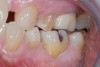

A 61-year-old female patient presented with a failed alloy restoration and missing the entire lingual surface of tooth No. 19 (Figure 2 and Figure 3). The argument could have been made to use either an onlay or a crown to replace the affected tooth. With the extent of the missing tooth structure, the malocclusion, and the patient's history of bruxism, treatment with a full-coverage restoration was selected to maximize longevity.

(2.) Preoperative images.

Figure 2

(3.) Preoperative images.

Figure 3